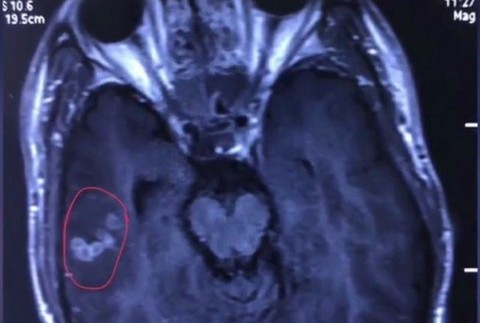

NAN / ČCHANG - S obrovskými bolesťami hlavy, ktoré sa už podľa neho nedali vydržať, sa obrátil na lekárov v čínskom meste Nan-čchang 26-ročný pacient. Toho okrem toho trápili aj epileptické záchvaty, hoci nikdy pred tým ich nemal. Odborníci dlho nevedeli prísť na to, čo mu je. Nakoniec mu priamo v mozgu našli pásomnicu. Keď ju z jeho hlavy odstraňovali, ešte stále bola živá.

Pacient, ktorý zverejnil len meno Liu podstúpil sériu vyšetrení, vrátane rozboru krvi. A práve tie odhalili v tele prítomnosť parazita. Pásomnica rodu spirometra sa nachádzala v jeho mozgu. "Červ bol ešte živý, keď sme ho vyťahovali. Bol aktívny, celý biely a skvelo plával," popísal zákrok lekár Wang Chunliang pre portál South China Morning Post.

Červ v mozgu Číňana